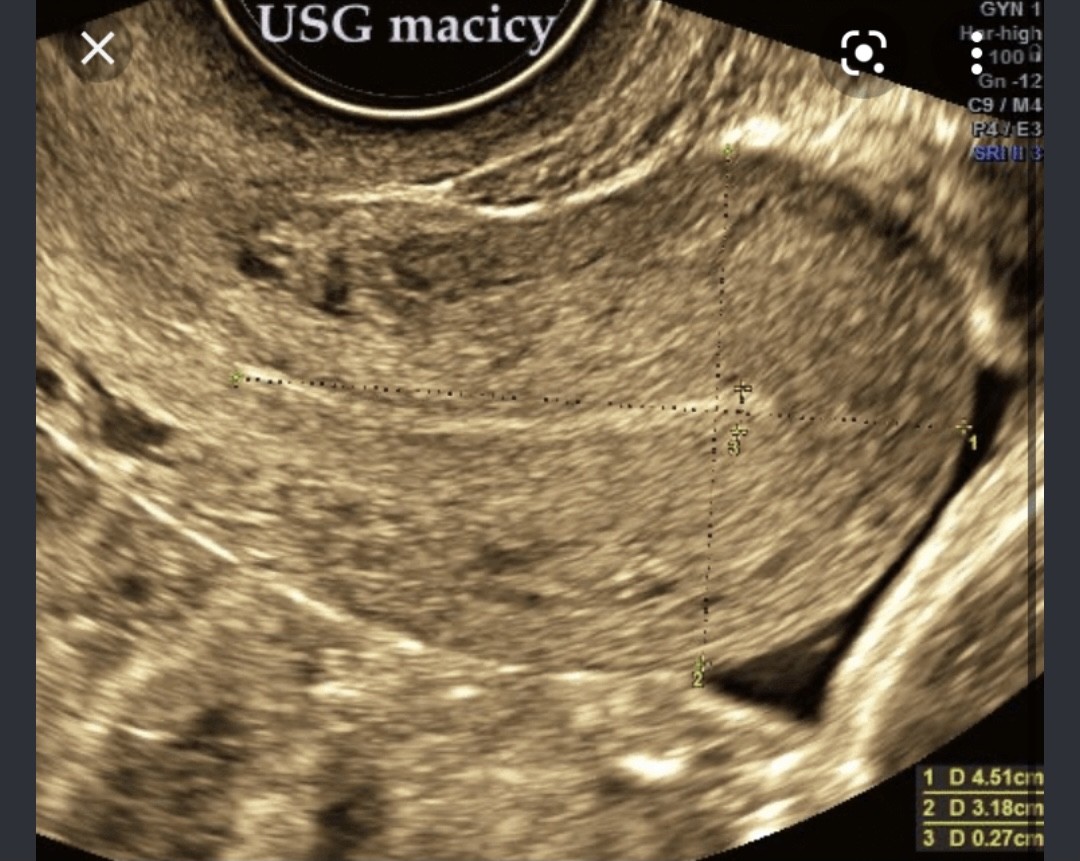

Według mnie opis masz dobry. Ciąży tam nie stwierdzono. Dla pewności może wróć się do lekarza i niech dopisze jeśli tak bardzo potrzebujesz mieć potwierdzenie